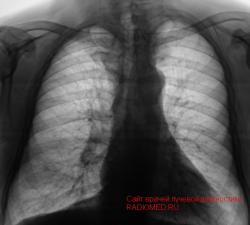

Пациент после расшифровки флюорограмм "взят на контроль" с учетом тени правого корня.

Произведена рентгенография в прямой стандартной проекции.

1.JPG